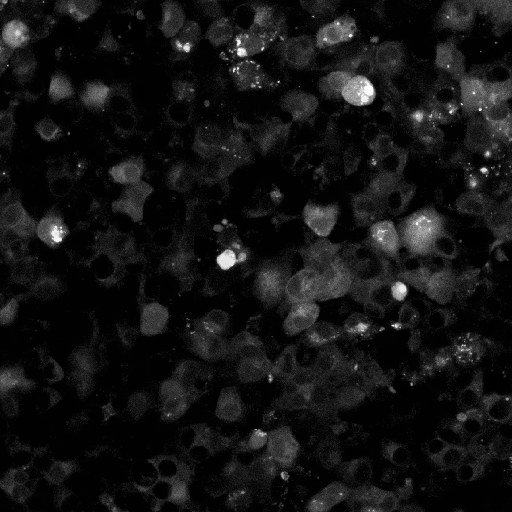

Stratifying the data by the six projection methods (Figure 2) linked abnormally high BRISQUE values to images processed with PDP. These images also showed generally higher PIQE and NIQE scores than the other techniques. Qualitative inspection of images with the worst BRISQUE scores confirmed corruption (Figure 3(c)). As a result, PDP images were unusable for GT annotation and were discarded from further analysis.

To complement the quantitative analysis of NR-IQA scores and assess whether the chosen image quality metrics effectively correlate with changes in the visual quality of our microscopy images, we conducted a complementary qualitative analysis on an exemplary subset of the HL-1 dataset (N = 18). PIQE, NIQE and BRISQUE were individually sorted in ascending order to identify exemplary images scoring the closest values to the minima, median and maxima identified in Table 2. Results of this analysis are summarised in Figure 3. PIQE assigned the highest values (i.e., P = 79.07 and P = 79.76) to images characterised by high levels of blur (Figure 3c), penalising decreases in image sharpness and losses of fine details over other signs of image quality deterioration, including the high salt and pepper noise and low brightness observed in high and median quality images for PIQE (Figure 3b). Differently, NIQE and BRISQUE were shown to penalise images that were substantially degraded by the specific preprocessing pipeline applied, primarily images belonging to the PDP group, associated with the highest values for all three metrics (Figure 2). Both NIQE and BRISQE were proven sensitive to alterations of the original images, leading to the generation of artefacts introduced by the preprocessing pipeline and previously not observed within the raw frames. Examples of these alterations are visible from the exemplary median quality images reported for the two metrics (Figure 3b). NIQE was also shown to penalise low image contrast, considering images characterised by high foreground-to-background contrast of higher quality than images characterised by low brightness and low illumination variability between cellular and background structures.

Highest quality images identified by the lowest PIQE, NIQE and BRISQUE scores were subjected to the expertise of an experimentalist researcher with extensive experience of working with signals from HL-1 networks, which empirically determined the existence of incongruencies between the perceived quality assigned by each NR-IQA score and the visual quality and usefulness of the image for GT annotation (see Section 6.2). Figure 4 reports the results of this analysis, comparing images identified of High Perceived Quality (HPQ) by PIQE, NIQE and BRISQUE scores (Figure 4a) with images considered to have better perceived quality by the expert. It is worth noticing that, while HPQ images identified by the experimentalist substantially outperform the quality of the best HPQ images identified by PIQE and BRISQUE, we found agreement between the HPQ images identified by NIQE and the ones chosen by the experimentalist, with three out of four images scoring similar NIQE scores to the HPQ images selected by the experimentalist. Oppositely, PIQE and BRISQUE showed incongruencies between the score assigned to the best (Figure 3a) and median quality images (Figure 3b) and the translation of these scores into the effective perceived quality of the images. Therefore, both scores assigned HPQ values to low brigthness images characterised by poor foreground-to-background contrast and extremely impaired visibility of regions of cellular density and most importantly of cellular boundaries, essential to allow the annotations of HL-1 images.

Amongst the six projection methods tested in the study, MIP, QP and SP methods were selected by the experimentalist as the methods yielding HPQ images (Figure 9). The preprocessing-projection combination methods selected were shown to generate images with high foreground-to-background contrast, which, together with high image brightness, facilitates the differentiation of cellular and background material in HL-1 images. These methods were also associated with an increased perceptive visibility and sharpness at cellular boundaries, making cell-to-cell connection more visible and facilitating the experimentalist in the recognition of cellular structures that characterise complex HL-1 networks for downstream GT annotation (as discussed in Section 6.2). Interestingly, CH and GH preprocessing methods in combination in two out of four of these methods, associated with MP and SP projections, and again in their lower value version (i.e., GL and CL) with SP projections and CL alone with QP methods (as shown in Figure 6). Notably, combined CH and GH approaches, preceded or followed by filtering methods, MB, NF and BF amongst the most common, also appear in the best methods combinations identified by PIQE, NIQE and BRISQE scores (see Figure 5). The value of using CLAHE with GF methods and NF techniques has been previously shown in medical imaging datasets [36], but never tested on FM datasets and in combination with projection methods for multi-temporal image fusion.